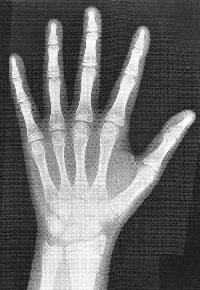

思春期の身長スパートは男女とも女性ホルモン(エストロゲン)に依存しています。エストロゲンは下垂体の成長ホルモン放出ホルモン受容体の感受性を増加させ、成長ホルモン分泌を増加させ、身長発育を促進させます。同時に、エストロゲンにより骨成熟が進行し、最終的には骨端線が閉鎖し、身長発育を停止させます。例えば、男児においてエストロゲン分泌が認められない病態では、男性ホルモン分泌は保たれていますが、骨成熟は進行せず骨端の閉鎖は起こりません。したがって、エストロゲンの骨成熟に果たす役割は明確です。女児の方が身長発育が早く、思春期獲得身長が小さいことは、女児の方がエストロゲンの産生量がより多く、骨成熟がより促進する為です。

思春期のスパート開始後、成人身長に達するまでの獲得身長は、思春期発来年齢が若いほど大きく、年長になるほど小さくなります。平均的な身長の小児では、身長スパート開始年齢を女児で9.5歳、男児で11歳とすると、その後の獲得身長は女児25cm、男児30cmです。